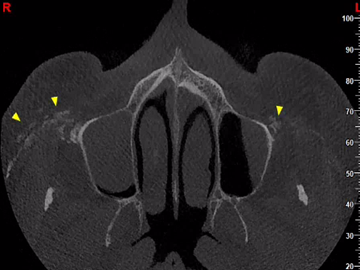

Απεικονιστικά παρατηρούνται πολλαπλές συρρέουσες υπέρπυκνες δομές μικρών διαστάσεων εντός των μαλακών μορίων και πλησίον του εξωτερικού τους περιγράμματος.

Συνήθης εντόπιση: